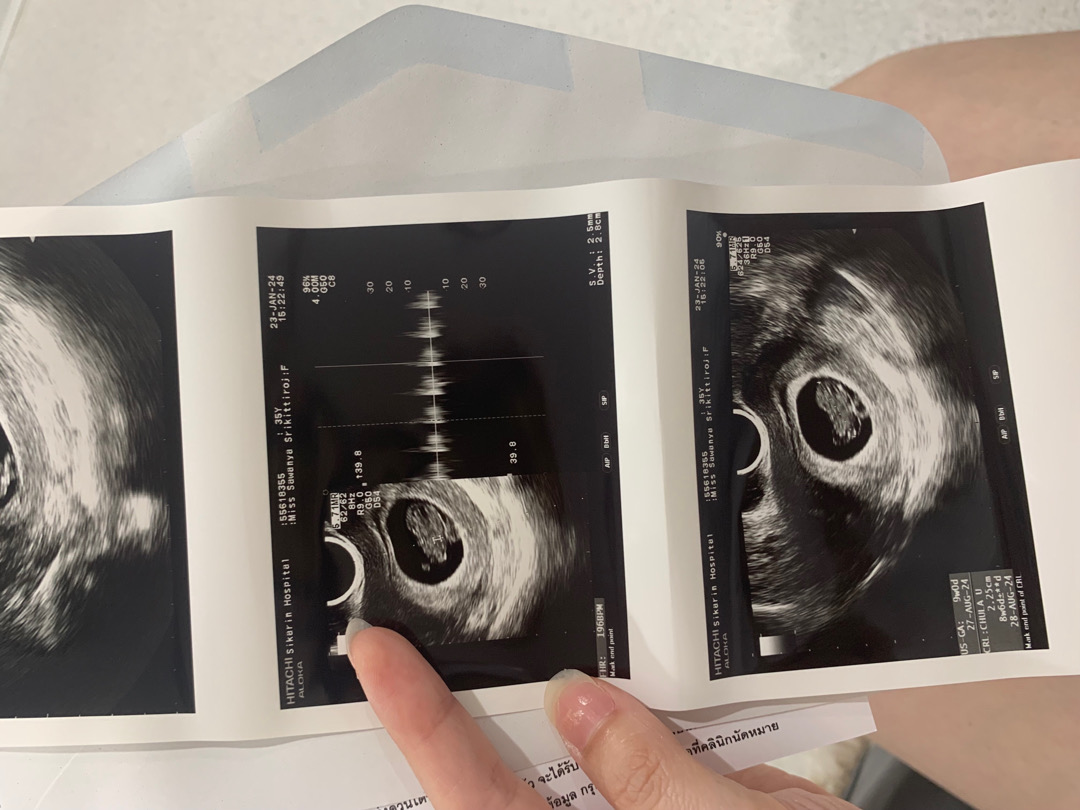

วันนี้ไปหาคุณหมอมา 8 วีคแล้วค่า แต่ยังซาวน์หน้าท้องไม่เจอ เลยต้องใส่เครื่องมือในช่องคลอด ชัดแจ๋วเลย คุณแม่ 8 วีคเป็นยังไงกันบ้างคะ ???

ทางนี้ไป 6 วีคทกับ 8 วีควันนี้ ยังซาวหน้าทัองเจอลางๆเองง่าหมอเลยต้องสอดเครื่องซาวเข้าไปในวัยวะค่ะ ขอยคุณนะคะ ครั้งหน้าหมอนัด 12 วีค ก้น่าจะ ซาวหน้าท้องได้ละเนอะ